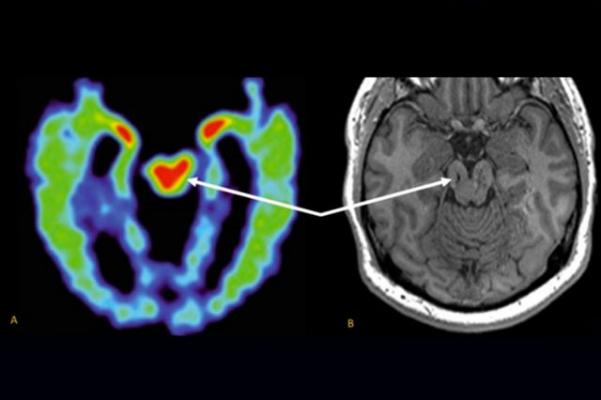

Unlike traditional psychiatry, which rarely looks at the brain, amen clinics uses brain imaging technology to identify hidden or undetected.